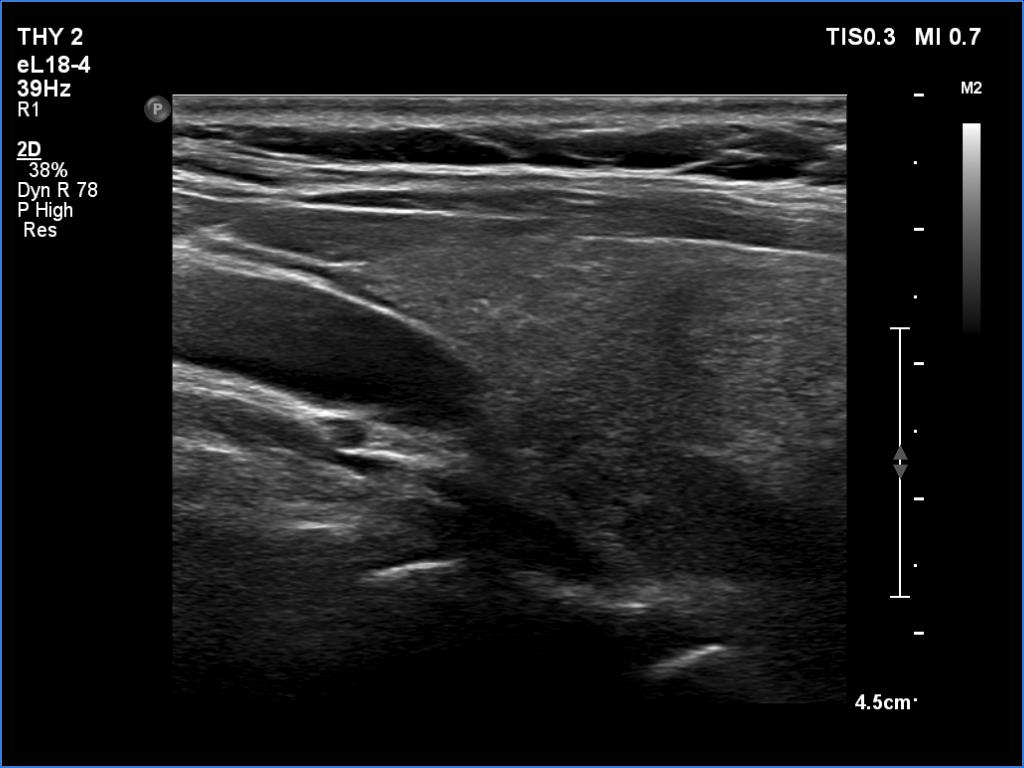

Clinical data: A 61-year-old woman was referred for preoperative localization of a parathyroid adenoma. The patient has been treated for hypothyroidism for seven years. Recently, hyperparathyroidism was diagnosed on evaluation of osteoporosis. MIBI scintigraphy disclosed increased uptake according to one of the left parathyroids.

Ultrasonography. The thyroid was moderately hypoechoic. There were two discrete lesions in the right lobe while a hypoechoic mass was found dorsal to the middle third of the left lobe.